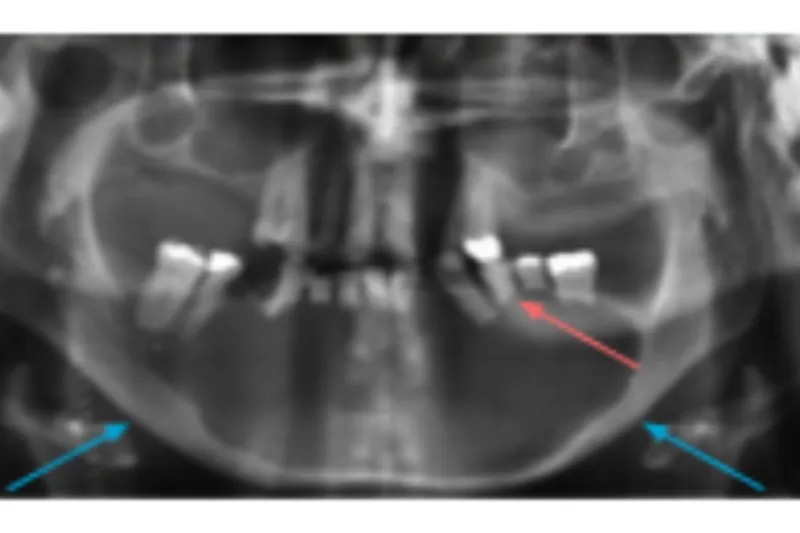

En 71-årig mand blev henvist til Kæbekirurgisk afdeling, Odense Universitetshospital, for diagnostik og behandling af hævelse i mandiblen.

Incisionsbiopsi blev foretaget for at fastslå diagnosen af den intraossøse proces.

Histologisk undersøgelse viste ukarakteristisk cyste på baggrund af sparsom vævsprøve.

Efter måneders drænbehandling blev forandringen enukleeret.

Fornyet histologisk undersøgelse af præparatet viste unicystisk ameloblastom af intraluminal og transmural type.